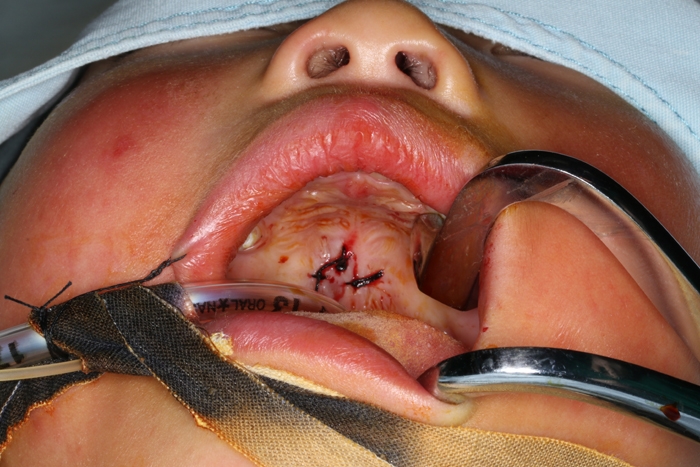

術(shù)后

取出的半截筷子

??? “慶幸的是,發(fā)生意外時,患兒手上拿的是竹筷子,比較脆,容易斷,如果當(dāng)時拿在手上的是木頭筷子或者金屬制的尖銳物,那孩子當(dāng)時倒地的一個沖擊力導(dǎo)致的可能就不是插在口腔上顎這么簡單了,可能會突破口腔,插入咽喉部或鼻腔內(nèi),再嚴(yán)重一些的插入顱腦也有可能?!毙灬t(yī)生介紹。